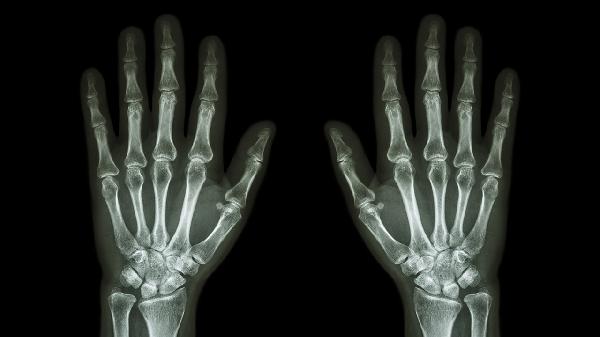

中指中关节软骨退变可能发展为骨关节炎。骨关节炎患者会出现关节压痛、变形,X线可见骨赘形成。治疗需控制体重减少关节负荷,配合氨基葡萄糖胶囊、硫酸软骨素片等软骨保护剂。疼痛明显时可短期使用依托考昔片,关节腔注射玻璃酸钠注射液有助于润滑关节。